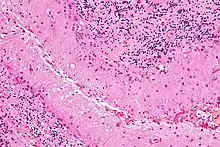

Micrograph showing Bergmann gliosis. H&E stain.

Bergmann glia (also known as radial epithelial cells, Golgi epithelial cells, or radial astrocytes) are unipolar astrocytes derived from radial glia that are intimately associated with Purkinje cells in the cerebellum.[10] Since bergmann glia appear to persist in the cerebellum, and perform many of the roles characteristic of astrocytes, they have also been called "specialized astrocytes."[9] Bergmann glia have multiple radial processes that extend across the molecular layer of the cerebellar cortex and terminate at the pial surface as a bulbous endfoot.[11] Bergmann glial cells assist with the migration of granule cells, guiding the small neurons from the external granular layer down to the internal granular layer along their extensive radial processes.[12][13] Besides their role in early development of the cerebellum, Bergmann glia are also required for synaptic pruning.[14] Following Purkinje cell death induced by CNS injury, Bergmann glia undergo extensive proliferative changes so as to replace lost or damaged tissue in a process known as gliosis.[15][16]